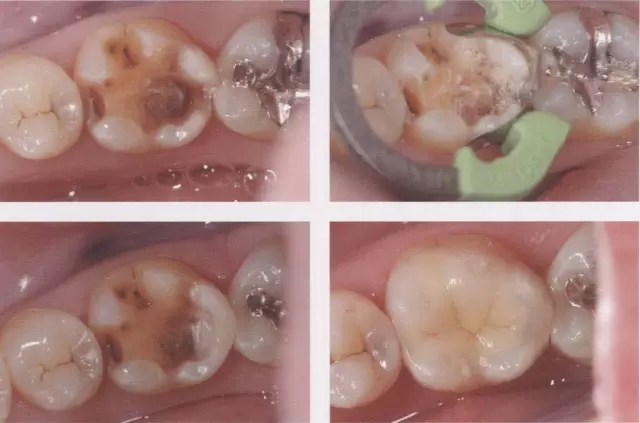

圖3 鄰接面成形困難的病例。如圖所示右下7近中傾斜,窩洞成形的遠中側(cè)有缺損(上左),所以遠中部需要在齦下做很深的成形(上右),因而選擇在遠中先進行樹脂填充后(上右)。進行MO窩洞修整后做全瓷嵌體試戴(下)。